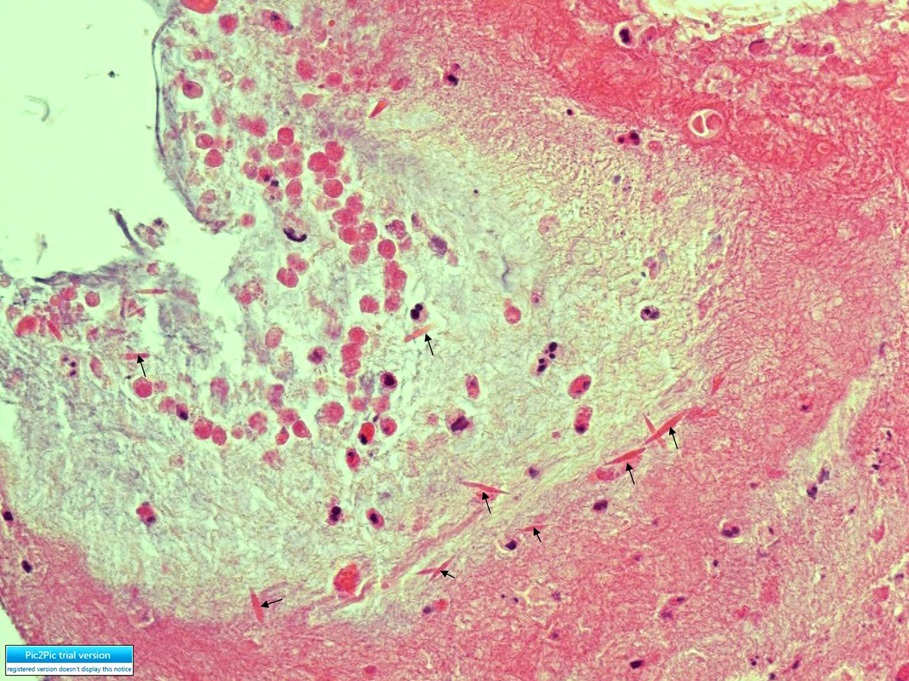

F/27

C.C : 2°³¿ù ÀüºÎÅÍ ¹Ýº¹µÇ´Â cough, sputum, rhinorrhea.

P/Ex. : wheezing on both lower lung fields.

Chest PA, Chest CT, Bronchoscopy , M-test was done.

Methacholine bronchial challenge test (+)